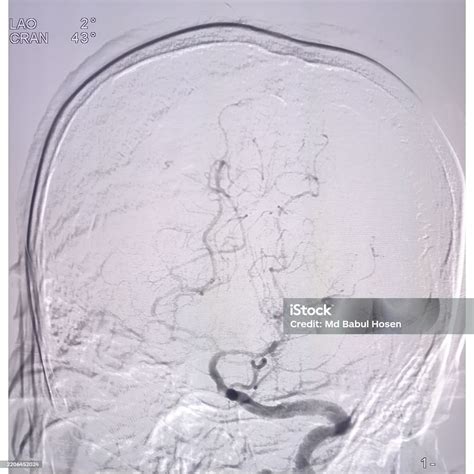

At its core, Digital Subtraction Angiography is a fluoroscopic technique that uses a computer-aided process to subtract the background image from a subsequent image taken after the injection of a contrast agent. The process begins with a "mask" image, which captures the anatomy of the target area without any contrast. Once the radiopaque contrast dye is injected into the bloodstream, a second set of images is captured. The computer then mathematically subtracts the mask from the contrast-filled images, leaving only the opacified vessels visible on the screen.

This process effectively removes visual "noise," allowing interventional radiologists to see even the smallest branches of an artery. Because of its superior contrast sensitivity and spatial resolution, it remains the preferred method for assessing conditions like aneurysms, stenosis, and arteriovenous malformations.

• Cerebrovascular Imaging: Used extensively to map the blood supply to the brain, helping detect aneurysms, carotid artery stenosis, or ischemic strokes.